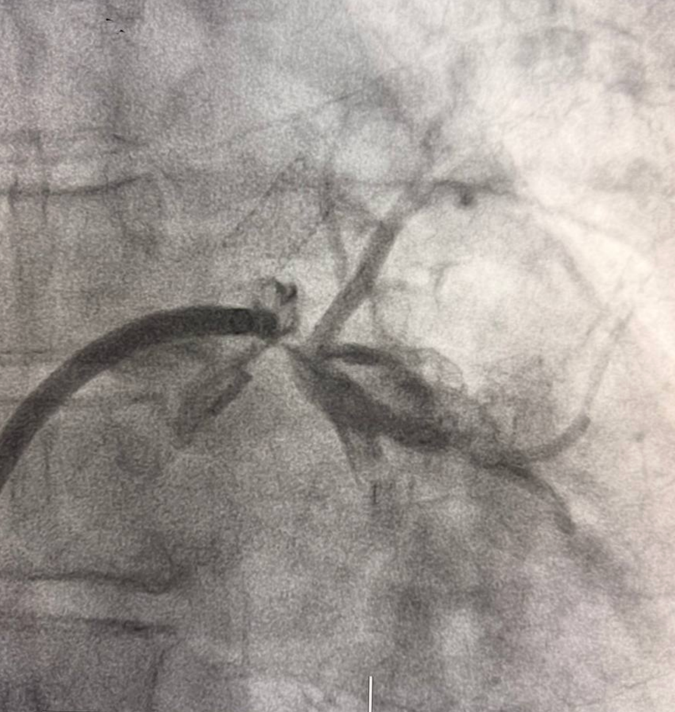

Пациент М., 54 лет наблюдался с длительной историей нарушений ритма сердца. Ранее ему была выполнена криоабляция, а спустя два года — радиочастотная абляция. Через два месяца после РЧА у пациента появились выраженная слабость и одышка при физической нагрузке. При дообследовании выявлены окклюзии левой верхней и левой нижней легочных вен.

Вмешательство проводилось через бедренный венозный доступ под местной анестезией. Основная сложность операции заключалась в полной окклюзии обеих легочных вен и необходимости точной навигации инструментов в условиях ограниченной визуализации. После реканализации поражённых участков были имплантированы стенты, обеспечившие надёжное восстановление просвета сосудов и полноценный венозный отток из лёгких.

В результате кровоток по левой верхней и левой нижней легочным венам полностью восстановлен. Состояние пациента стабилизировалось, одышка регрессировала. В настоящее время пациент чувствует себя хорошо.